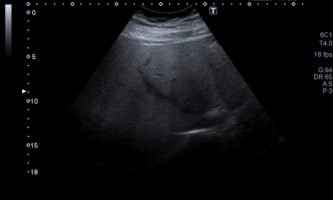

El médico de referencia le indica nueva ecografía de control, donde se observan múltiples y extensas lesiones focales hepáticas hiperecogénicas, redondeadas y confluentes, las cuales predominan en adyacencia a venas supra hepáticas, sin condicionar efecto de masa y sin alteración de la superficie hepática(fig. 1 y 2). Ante la valoración con Doppler color no presenta patrón de flujo peri ni intralesional y respeta el calibre de las venas supra hepáticas(fig. 3 y 4). Dada las características ecográficas se sospecha esteatosis focal multinodular confluente como principal diagnóstico presuntivo, siendo los diagnósticos diferenciales patologías de naturaleza infecciosa, tumoral o metastásica.